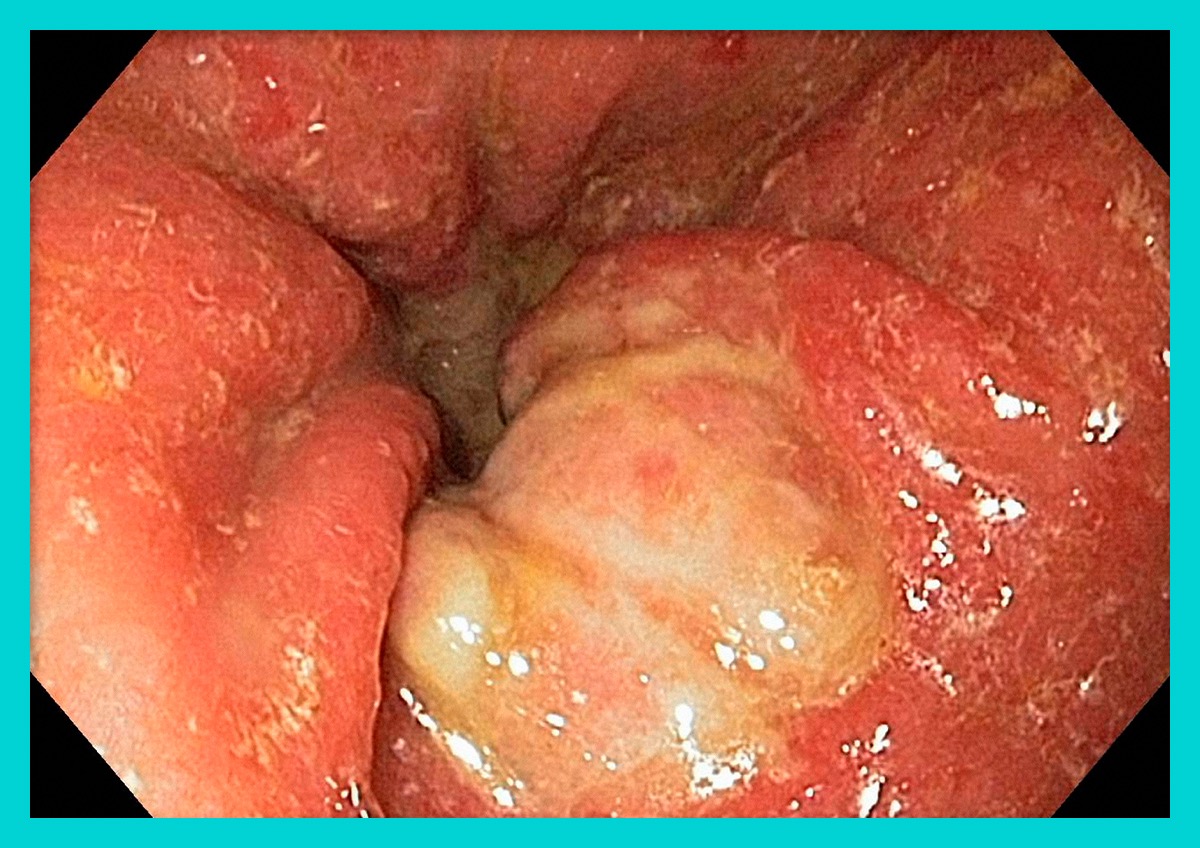

- 위내시경 검사: 위암 진단의 가장 정확한 방법으로, 직접 위 내부를 관찰하고 의심 부위의 조직검사도 가능합니다. 최근에는 수면내시경으로 편안하게 검사받을 수 있습니다.

- 내시경적 치료: 조기 위암 중 림프절 전이 가능성이 거의 없는 경우 내시경으로 종양만 제거하는 치료입니다. 내시경적 점막하 박리술(ESD)이 대표적이며, 위를 보존할 수 있는 장점이 있습니다.